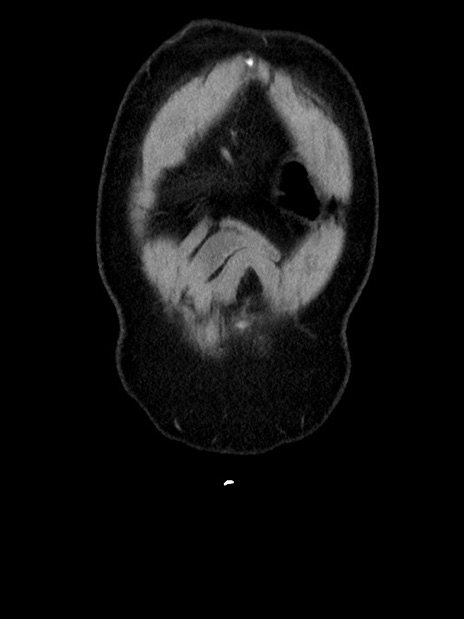

横断像

【症例】70歳代 男性

【主訴】腹部膨満、嘔吐

【現病歴】昨日より腹部膨満感出現。本日増悪し、仙痛出現。嘔吐あり、受診。

【既往歴】糖尿病、胆摘後

【身体所見】BP 149/80mmHg、HR 74/min、BT 35.9℃、腹部:膨満、軟、圧痛なし。腸雑音減弱あり。上腹部正中切開瘢痕あり。

【データ】WBC 13500、CRP 1.72